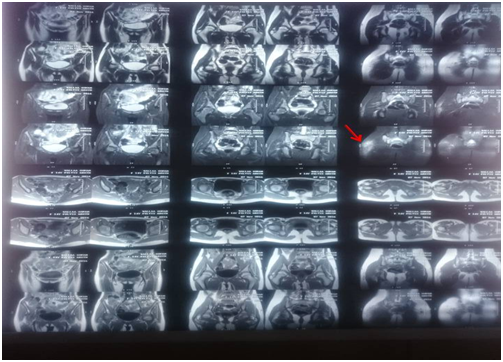

15 yrs old female patient born and lives in Kafr Elsheikh, Egypt was diagnosed to have typical attacks of FMF 5 years ago on colchicine treatment (1.2 mg/d), Molecular genetic study revealed positive heterozygous state , MEFV gene mutations (M694V , E148Q , P369S). The patient has positive family history (her father and uncle has FMF), During the past 6 months, the patient experienced bilateral diffuse, non exertional crippling muscle ach with swelling of both thighs restricting movement of lower limbs, not relieved by colchicin or NSAIDS, the condition was not associated with fever and colicky abdominal pain or skin rash for which she was admitted in the hospital of the faculty of medicine Alex University where initial examination and investigations were done then the patient sought a medical advice in our department. On systematic physical review: The well-developed patient was bedridden in agony normal blood pressure and temperature. Height=145 cms, weight=40 kgs, BMI=19. There was bilateral symmetrical diffuse& tender swelling of both thighs with subcutaneous edema made her unable to move the lower limbs properly, sensory and motor exam of the upper extremities was normal, Cardiac, chest, abdominal examination was apparently free. Laboratory investigations revealed normal levels of CK, CK-MB, Aldolase & transaminases. Hemoglobin 13.8 g/dL; white blood cell count 5000/mm3, platelet count, 209,000/mm3; ESR was 14mm/h and high C-reactive protein (CRP) (40 Iu/L). Normal liver & kidney function tests. ASOT within normal range (150 U/ml), ANA, ANC, RF & amyloid A were negative virology markers for HCV, HBV& CMV. Chest X-ray, Abdominal ultrasonography, bilateral lower limb arterial and venous duplex & Ultrasound knee joint showed no abnormalities. MRI of both thigh on presentation showed right posterolateral thigh ill defined patchy area of soft tissue edema involving subcutaneous tissue eliciting high signal in STIR & measure about 10 cm, normal MR musculature appearance with intact intermuscular fascial fat planes (Figure 1)(Figure 2).

Figure 1 Intermuscular fascial fat planes.

MRI can be considerd as a valuable tool to diagnose PFMS, the features that suggest PFMS are diffuse oedema of subcutaneous fat tissue, increased intensity and contrast enhancement of the muscles and increased signal intensity of vascular beds.15 Electromyogram (EMG) may be normal or show nonspecific myopathic changes, Muscle biopsy was not feasible in most of diagnosed cases, but of which was done revealed non specific inflammatory inflilteration with leucocytes, lymphocytes and eosinophills.

It was peculiar that our young lady case presented with atypical attack of FMF consisting of severe muscle pain & swelling affecting both thigh but not accompanied by fever, rash or abdominal pain o. Also ESR was not elevated as excepected there is no definite rational for that; yet the compliance of the patient to colchicine may abort the elevation of ESR as acute phase reactant. We began to revise the history and to put differential diagnosis. Myopathy related to FMF was on the top after exclusion of vasculitis. Hence Fulfiling the clinical criteria, normal CPK levels & characteristic MRI findings (oedema of subcutaneous fat tissue) together with the evidence of inflammatory myopathy by EMG are the hallmarks of diagnosing PFMS and excluding out the colchicines induced myopathy. Immediately, the decision was made based on the foregoing & Steriods were prescribed with collaporation of physiotherapy team for more than 2 months a good response was achieved and the patient was able to move independently